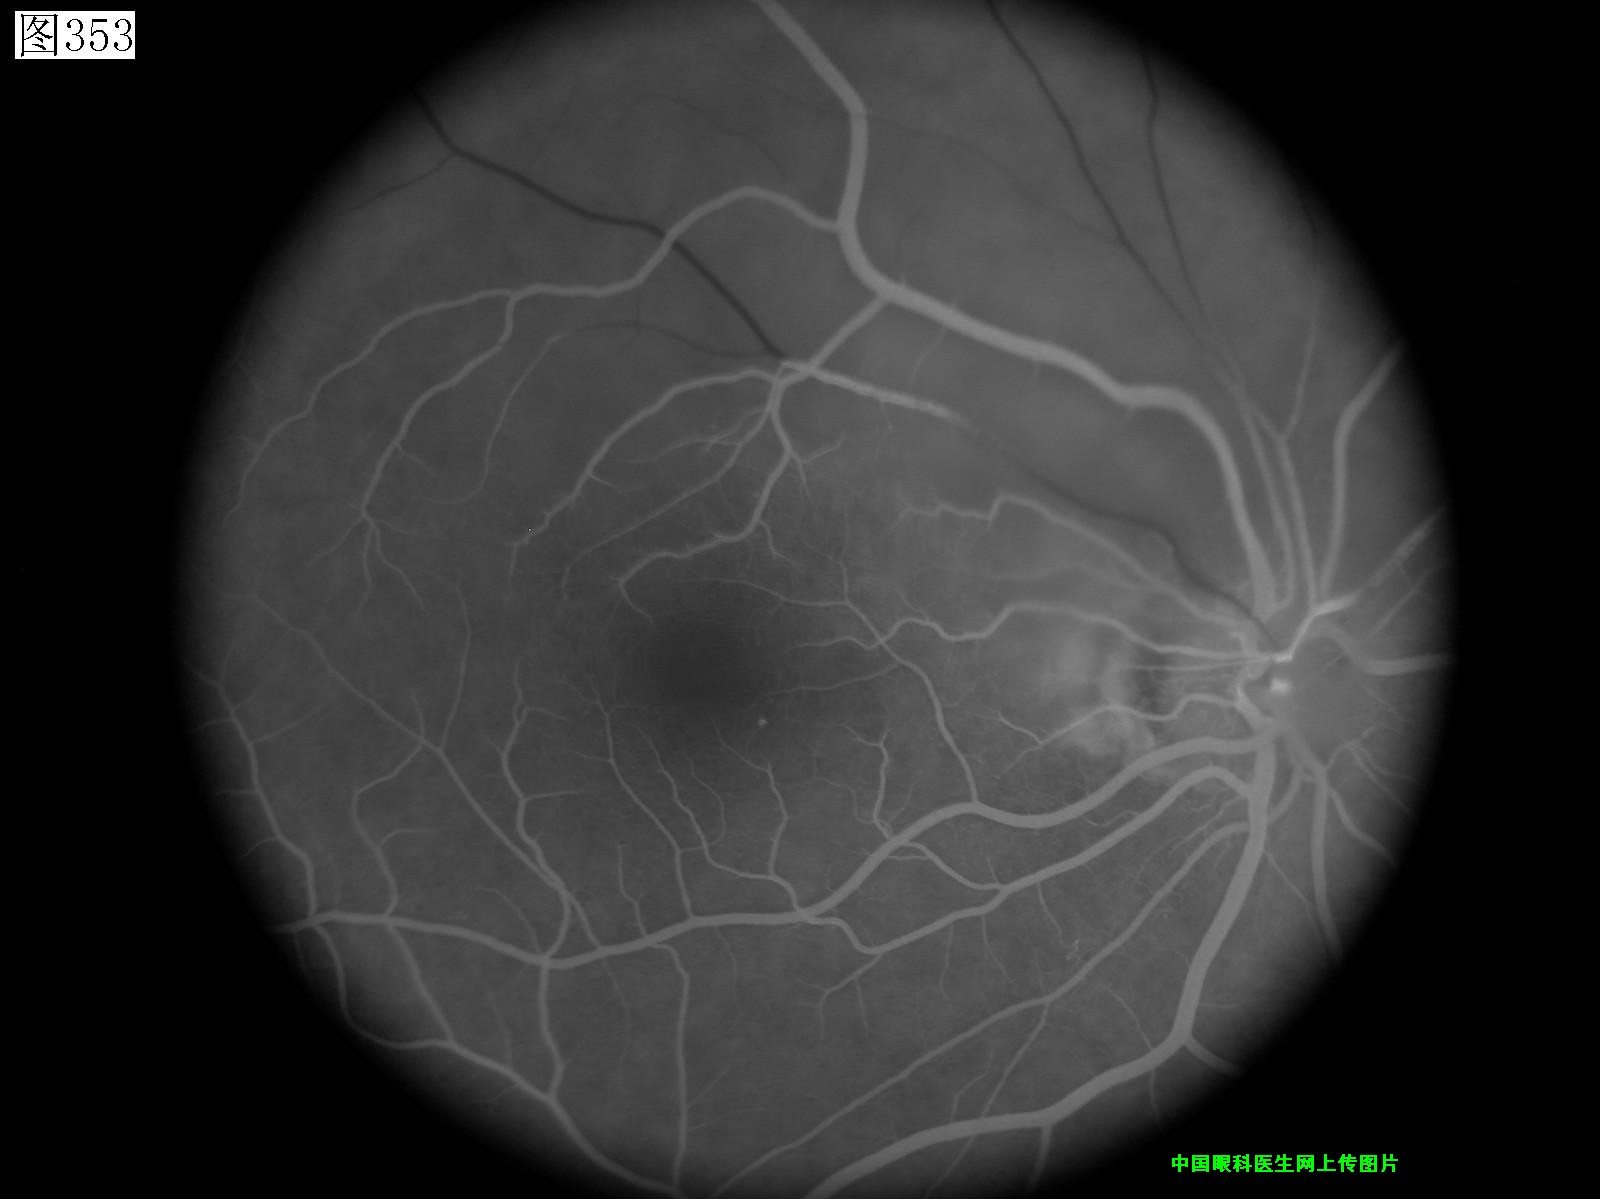

353 354 355 356